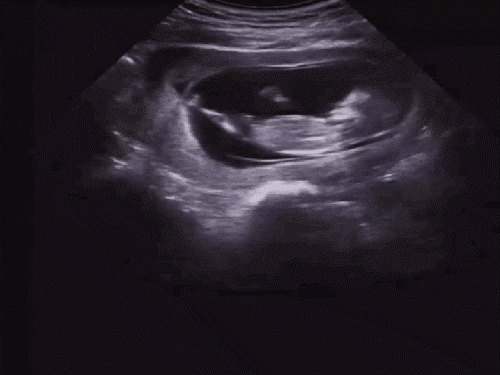

검사 중 킥 실력을 자랑하는 오뜨ㅋㅋ

초음파로 어떤 걸 보는지 검사 리뷰 같은 걸 공유해볼게요 ~^^

우선 1차기형아검사 초음파에서 제일 먼저 확인했던 머리~꼬리뼈의 길이 ㅎㅎ #임신 12주차 정도가 되면 6~7cm 정도가 된다고 합니다. ^^

그다음에 본 뇌!# 임신기형아 검사를 통해 뇌 초음파는 처음 봤는데 뇌가 나비 모양이었죠? 다들 알고 계셨군요…굉장히 신기했던 뇌가 나비 모양으로 잘 성장했는지 머리 옆의 길이를 쟀습니다. 가로 길이는 2cm 정도 나왔습니다. ~

그리고 그 유명한 #목투명대 검사! 목투명대가 너무 두꺼우면 다운증후군과 에드워드 증후군이 있을 확률이 높대요 ㅠㅠ목투명대는 3mm를 넘으면 안된다고 하셨는데, 오토는 1.7mm로 통과했습니다 휴~

안녕하세요~~해주는 오토 그리고 또 코가 잘 자라는지 확인하는데 이것도 다운증후군과 관계가 있다고 하네요.다행히 코뼈도 멋있네요.손가락도 딱 다섯개 ㅎㅎ 이미 뼈가 생겼어요! 손으로 안녕~ 하고 인사하는 것 같다고 남편이랑 두근두근하고 있어…ㅋㅋㅋㅋㅋㅋㅋ

심장 박동도 확인해주시고요153비트가 나왔는데 정상이라고 하더라고요.